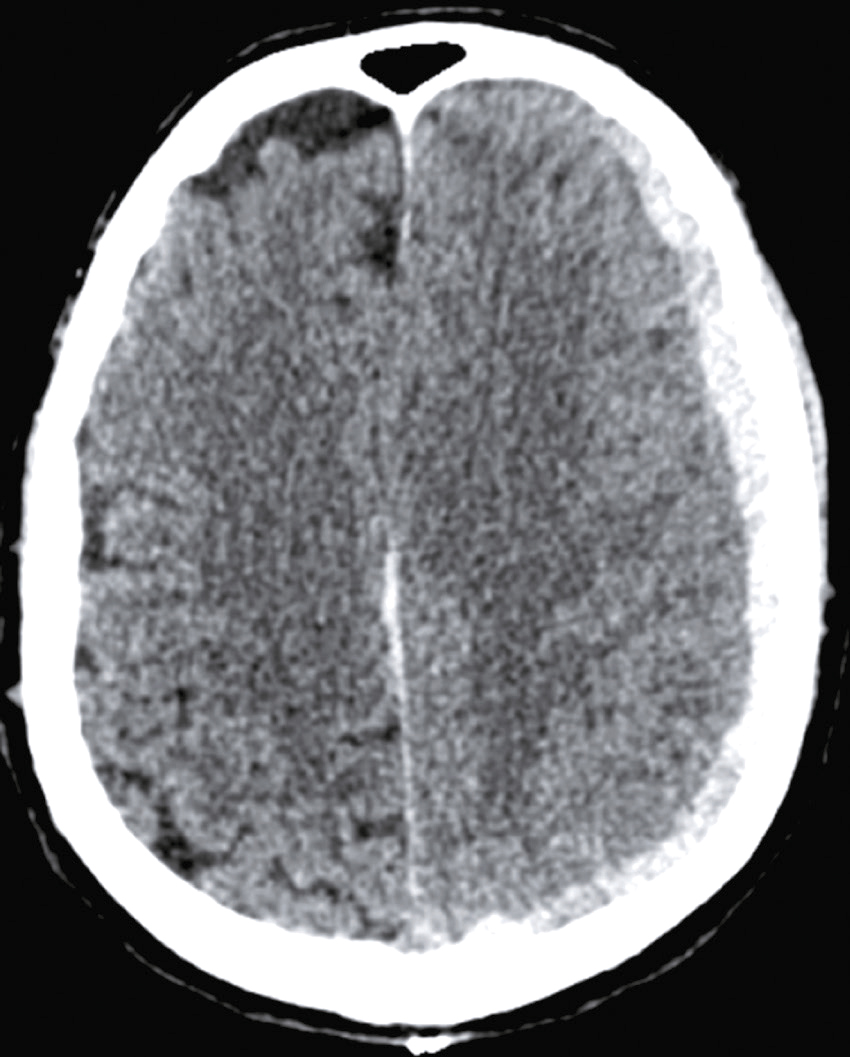

Question 3 – QRMDans l’hypothèse d’une hémorragie méningée, un scanner cérébral sans injection de produit de contraste est réalisé en urgence, quelle(s) anomalie(s) confirmerai(en)t le diagnostic ?

Question 4 – QRMVoici une coupe axiale d’un scanner cérébral sans injection (fig. 31.9). Concernant son interprétation, quelle(s) est (sont) la (les) proposition(s) exacte(s) ?

Fig. 31.9 L'image montre une coupe transversale d'un scanner cérébral (CT scan) d'un cerveau humain. Cette image en noir et blanc présente des détails anatomiques du cerveau, y compris les structures internes et les contours du crâne. Les zones claires représentent les tissus osseux, tandis que les zones sombres indiquent les tissus mous du cerveau. On peut observer des variations dans les nuances de gris qui révèlent différentes densités de tissus. Les ventricules cérébraux, qui sont des cavités remplies de liquide céphalo-rachidien, sont également visibles au centre de l'image. Ces cavités apparaissent sombres en contraste avec les tissus environnants. La partie périphérique de l'image montre les os du crâne, apparaissant comme des lignes blanches bien définies. Les scanners cérébraux sont des outils essentiels pour diagnostiquer et surveiller diverses conditions neurologiques. Ils permettent de détecter des anomalies telles que des hémorragies, des tumeurs ou des lésions cérébrales. Les variations de teintes visibles sur l'image aident à différencier les structures et à évaluer leur état, fournissant ainsi des informations cruciales pour les professionnels de la santé. Grâce à ces images détaillées, il est possible de planifier des traitements adaptés et de surveiller l'évolution des pathologies cérébrales.

- A hyperdensité spontanée des vallées sylviennes

- B hyperdensité spontanée du sinus maxillaire droit

- C hypodensité spontanée de l’épiphyse

- D hyperdensité spontanée du 4e ventricule

-

E hypodensité spontanée des plexus choroïdes